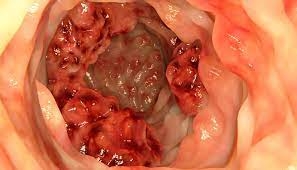

Considerado o terceiro tipo de câncer mais frequente em homens, após o de próstata e o de pulmão, e o segundo entre as mulheres, após o câncer de mama, o câncer colorretal é um tumor que acomete o intestino grosso. “Importante ressaltar que o câncer de intestino é tratável e, na maioria dos casos, curável, ao ser detectado precocemente”, observa o coloproctologista Mardem Machado, credenciado ao Mato Grosso Saúde pela Clínica Vida.

O diagnóstico do câncer de intestino é feito a partir de um exame clínico e físico, incluindo o exame proctológico, a retossigmoidoscopia, a colonoscopia e exames de sangue. “Assim que o paciente é diagnosticado, ele inicia o tratamento”.